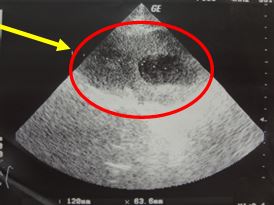

+ Siêu âm tim: Buồng thất trái giãn, chức năng tâm thu thất trái giảm. Hở hai lá nhẹ; hở chủ nhẹ, tăng áp lực động mạch phổi nhẹ. EF 37%.

Hình 3. Hình ảnh siêu âm tim